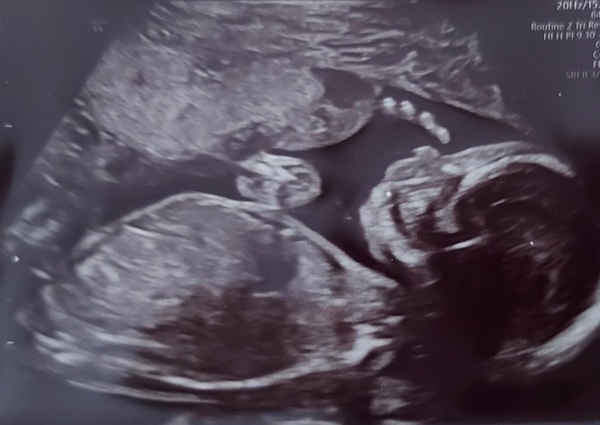

Congrats to those who have had their 20w scans, lovely pics of your little ones - can't believe we're half way!

Beautiful scans everybody 🥰

Congrats @Carefree1 I also had my 20w yesterday. My husband knows the gender and he is going to surprise me next week! Its weird him knowing but it is exciting.

Lovely scan photo @Carefree1 - congratulations!